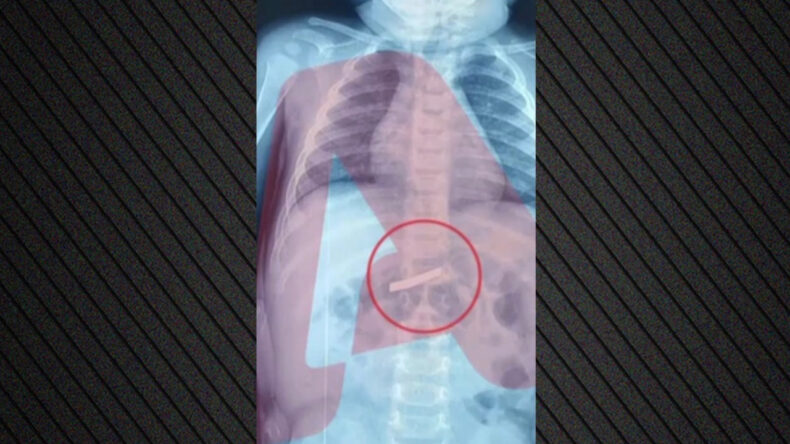

Durumu Atina'daki Çocuk Hastanesi'nde doktorlara anlatan ebeveynler, doktorların yönlendirmesi doğrultusunda röntgen çekilmesine karar verdi. Röntgen sonuçlarında çocuğun midesindeki jilet net bir şekilde tespit edildi.

Yapılan ameliyat ile jilet başarıyla çıkarıldı ve doktorlar, çocuğun sağlık durumunun iyi olduğunu bildirdi.